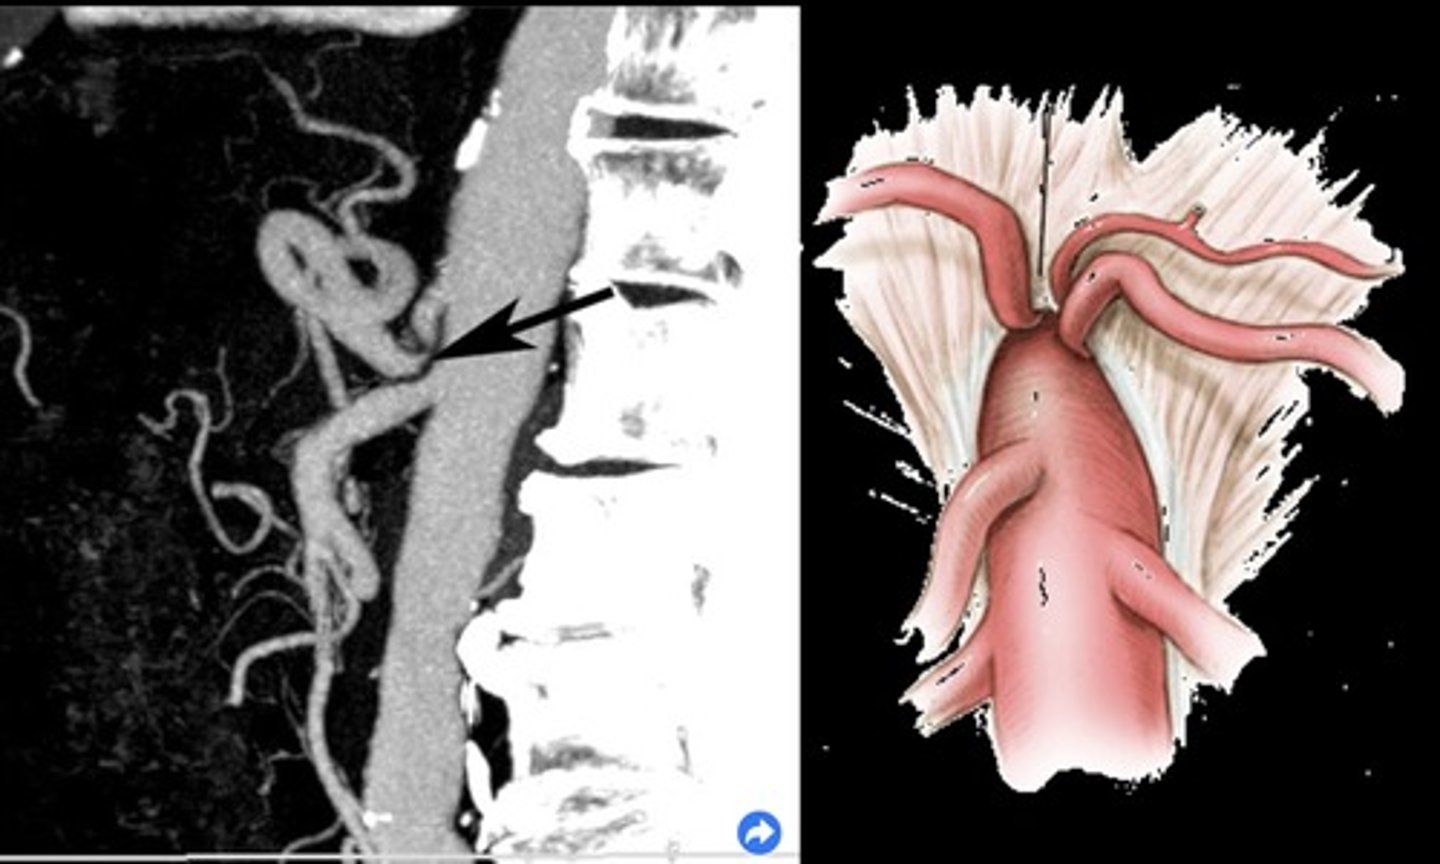

Common Trunk Variant

Celiac and SMA come off common trunk

Median Arcuate Ligament Syndrome (MALS)

Compression of celiac axis during exhalation by median arcuate ligament

Pain relieved by inhalation

Evaluate in supine & upright positions and with inspiration & expiration

Celiac Artery PSV with MALS

> 250 cm/sec during expiration that normalizes with inspiration